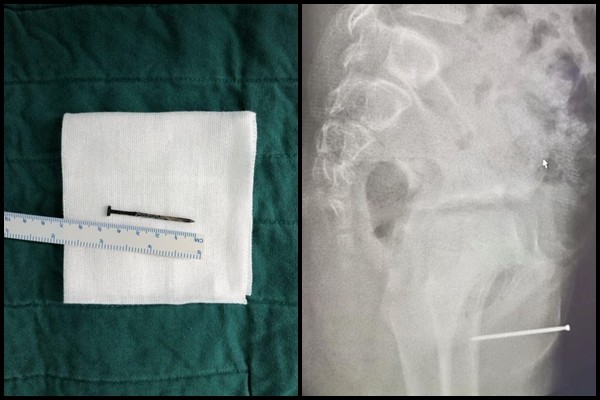

▲男童將鐵釘插入自己尿道,導致下體流膿。(圖/翻攝自騰訊網)

▼充滿鏽蝕痕跡。(圖/翻攝自騰訊網)

據悉,這根鐵釘長約4.7公分,佈滿生鏽痕跡,手術中還發現男童尿道黏膜充血並有部分損傷。醫生詢問男童這些東西是什麼時候塞進去的?怎麼塞進去的?對方卻答不出來。醫生指出,因為尿道異物或者陰道異物入院的兒童並不少見,由於孩子大多無知、好奇、或是想緩解瘙癢才會將異物塞入尿道。